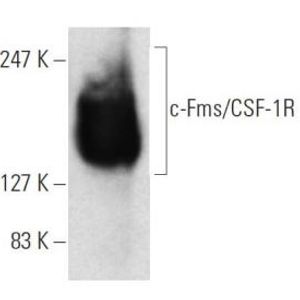

AUG 07, 2023CancerAn exciting new cancer drug has recently entered into a phase 1 clinical trial supported by promising pre-clinical work. ...